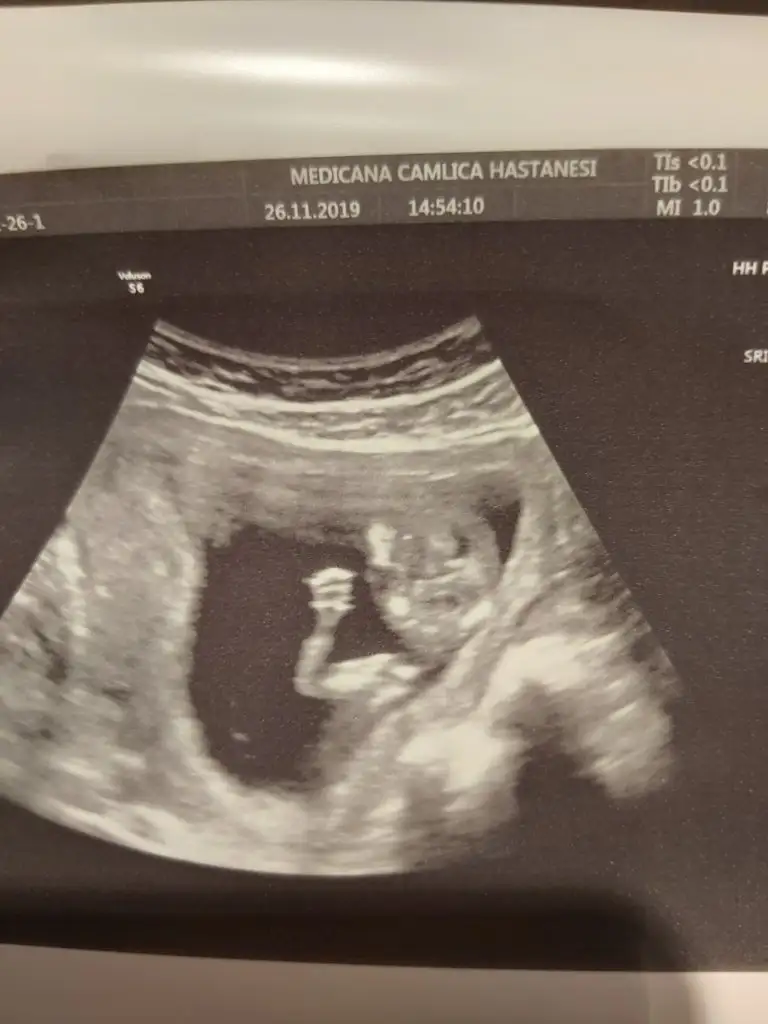

Bana da de banada attım resminiaaa nuba göre erkek canm kaç haftalıktı bu usg

Erkek mi ki acabaTeyzeler bu da bizim fotomuz ☺

Kız gb sanki ya ben hıc anlamam daNub ne kızlar ben bilmiyorum bende attım banada tahmin edin kim anlıyorsa size el salladık hatta aşk olsun kızlar![]()